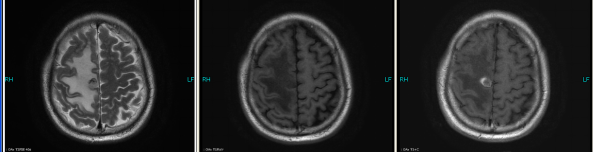

The patient checked for further treatment on November 23, 2015. A pre-chemotherapy assessment was made and the results showed multiple bone metastases and multiple enlarged lymph nodes in the left shoulder blade, the fourth lumbar, the right iliac bone and other locations. Performance status (PS) was only one point. Pemetrexed Disodium (500 mg/m2 d1) + Carboplatin (AUC 5 d1) + Bevacizumab (7.5 mg/Kg d1) was administered beginning November 26, 2015 for the chemotherapy treatment and supportive therapy was provided, such as, dehydration, reduction of intracranial pressure, promotion of bone repair, pain relief, and waist protection. After discharge, the coughing basically disappeared and the dizziness, backaches, and hemiparesthesia of the left side were significantly improved. Patient emotional state and sleep quality was significantly improved. It was basically normal after a routine blood examination. A second chemotherapy treatment was successfully completed on December 18 (the program is idem). The patient returned to the hospital on January 6, 2016 and was proposed for a third chemotherapy. The pre-chemotherapy assessment showed that the measurable, targeted right lung lesion had decreased (3.2 mm, with a rate of decrease 44.8 %) (Fig. 1D). Lymphangitis carcinomatosa was significantly decreased and right frontal nodulus lesions were reduced significantly (Fig. 2C). No new lesions were found. Efficacy was assessed as partial relief (PR). A third and fourth chemotherapies were completed on January 9 and January 30, 2016. Efficacy was re-assessed as PR (Fig. 1E) with lung CT review as an outpatient on February 11. Since then, the patient had been subjected to a combined administration program of pemetrexed disodium (500 mg/m2 d1) + bevacizumab (7.5 mg/Kg d1) for continued chemotherapy. A lung CT and a cranial MRI were peformed on April 16. The results showed that the control of lung lesions and intracranial lesions were basically the same as before (Fig.1F and Fig. 2D). The patient had no cough, backaches, or hemiparesthesia and the quality life significantly improved. PS was decreased to zero.